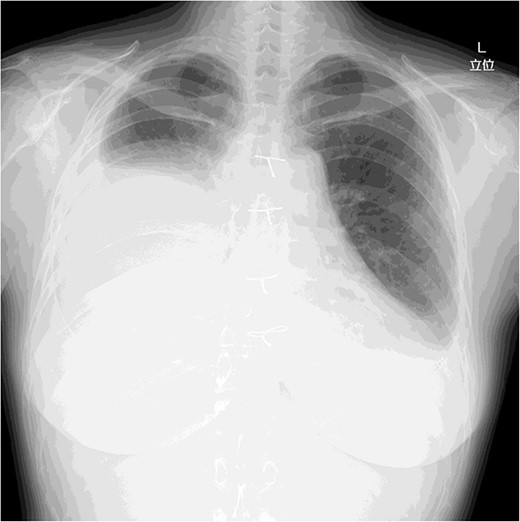

A 46-year-old woman presented to a previous hospital with an abnormal shadow on a chest X-ray. Computed tomography (CT) revealed an anterior mediastinal mass lesion with its largest diameter of 6.6 cm (Fig. 1). Therefore, she was referred to our hospital with suspicious mediastinal malignancy. All tumor markers examined were within normal limits.

Under general anesthesia, she underwent total thymectomy via median sternotomy. Her post-operative course was uneventful and there was no visible chyle leakage from the chest drainage tube. On post-operative day 2, the chest drainage tube was removed. The chest X-ray on post-operative day 7 revealed no massive pleural effusion (Fig. 2), and she was discharged on the day. The final pathological diagnosis was a Type A thymoma with Masaoka’s Stage I.

Chest X-ray on post-operative day 7 revealing no massive pleural effusion.